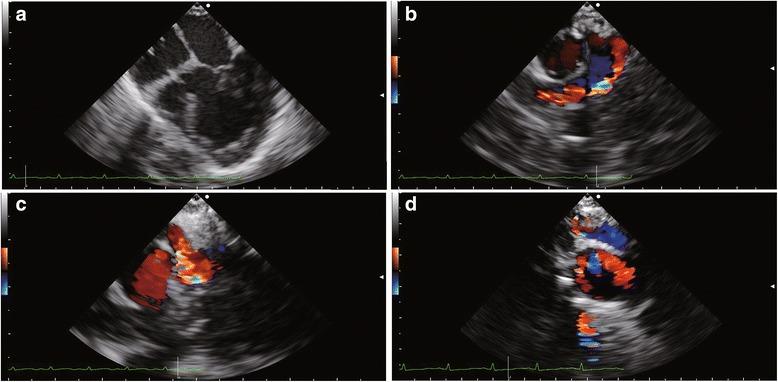

We report a case of tricuspid atresia patient who underwent first palliative surgery and second palliative surgery. Volume loading condition was assessed by energetic parameters (energy loss, kinetic energy) intraoperatively using vector flow mapping. These energetic parameters can simply indicate the volume loading condition.

Vector flow mapping was useful tool for monitoring volume loading condition in congenital heart disease surgery.